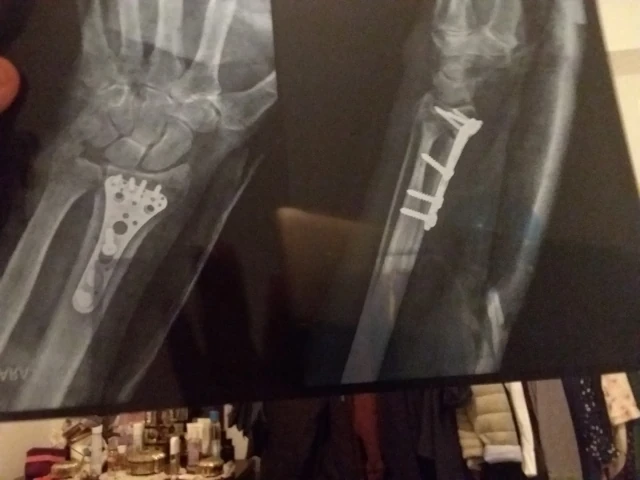

Ostéosynthèse de fracture de l'extrémité distale d'un os de l'avant-bras, à foyer ouvert

Ostéosynthèse de fracture ou de décollement épiphysaire de l'extrémité distale d'un os de l'avant-bras par broche, à foyer fermé

Réduction et fixation de fractures

Réparation de traumatismes musculo-squelettiques

Fracture

Fractures osseuses